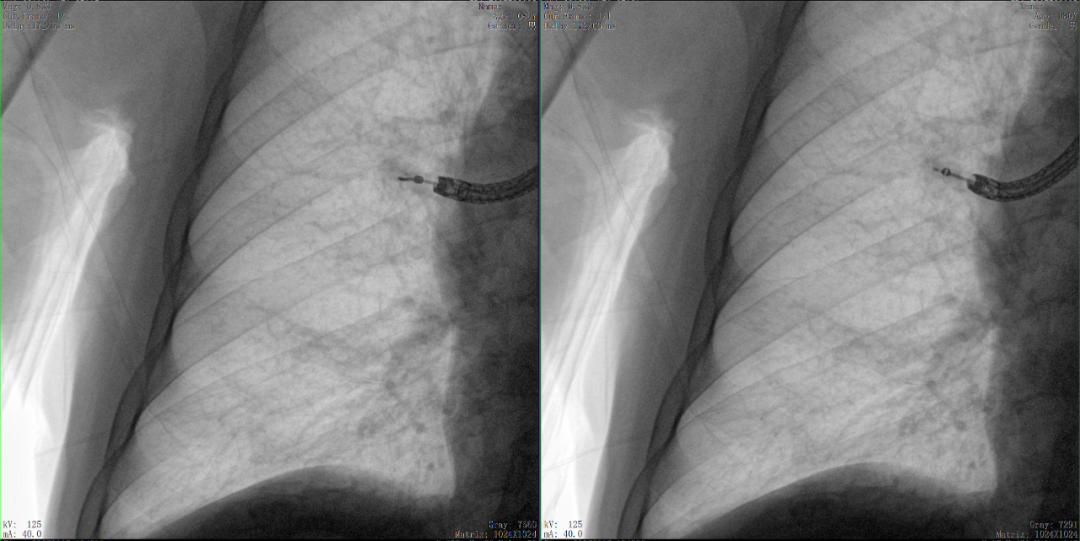

二維正側位影像

三維“類CT”影像

病例2 踝關節骨折復位(31歲)

在踝關節骨折復位手術中,用三維C可以更好地觀察骨折部位的復位情況:

正側位影像觀察脛腓聯合復位良好

從三維影像看,復位欠佳,貼合度不夠